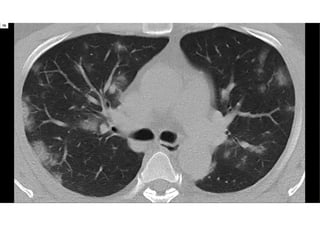

Tomografia

computadorizada

IMAGEM

O QUE É?

 Tomografia computadorizada é um procedimento não

invasivo de diagnóstico por imagem que combina o uso de

raio-x com computadores especialmente adaptados. É

utilizado para criar imagens detalhadas dos mais variados

tecidos do corpo humano.

 O procedimento é realizado através da emissão de raios X

rotacionada ao redor do corpo, que por sua vez e de forma

variada, a depender de cada tecido, atenua o feixe de raios-

X, que são absorvidos por detectores de radiação, que

enviam então os dados para um sistema computacional.

PECULIARIDADES

 A tomografia não oferece riscos ao paciente quando obedecida a periodicidade

e as recomendações do profissional responsável pelo exame.

 Por se tratar de um procedimento que utiliza raios-x para criar as imagens, é

fundamental não ultrapassar a dose anual de radiação recebida por esse tipo

de exame. Por isso, sua quantidade deve ser registrada no laudo. O recomendado

é que seja realizada no máximo uma vez por ano.

 Os maiores riscos que o paciente está sujeito ao realizar a tomografia estão

relacionados ao não cumprimento das orientações do médico ou técnico, que

pode desencadear uma reação ao contraste, por exemplo.